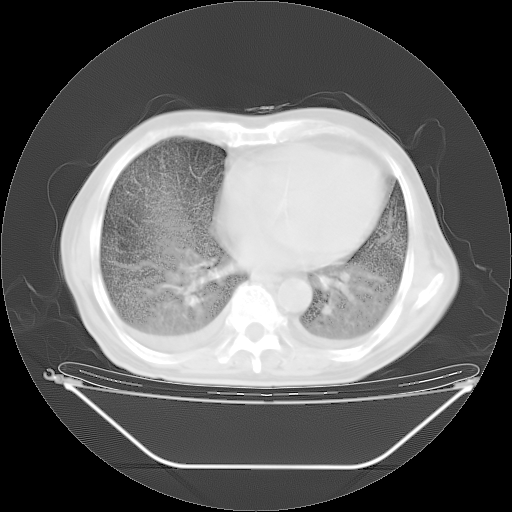

胸腹部CT,诊断意见:左上肺叶钙化灶、左侧胸膜局限性增厚并钙化、胆囊炎。描述部分肺组织呈磨玻璃样改变。

今天复查肺部CT,发现双肺广泛磨玻璃样改变。所以我把3月19日和5月9日相隔50天的肺部CT上传。请大家会诊。

2009年3月19日肺部CT片。

2009年3月19日肺部CT

大致读了系列胸部CT:纵隔窗无明显异常,肺窗:从4、27至今:主要是双肺中下野外带可见毛玻璃样改变,目前处于急性肺泡炎阶段,至于原因考虑1、结替组织或胶原血管性疾病所致?2、恶性疾病如恶组在肺部所致的表现或细支气管肺泡癌?3、药物或其它原因如肺蛋白沉着症所致肺泡炎目前不太可能?总之,明天就去请我院的呼吸科、感染科、血液科和临免专家会诊哈。